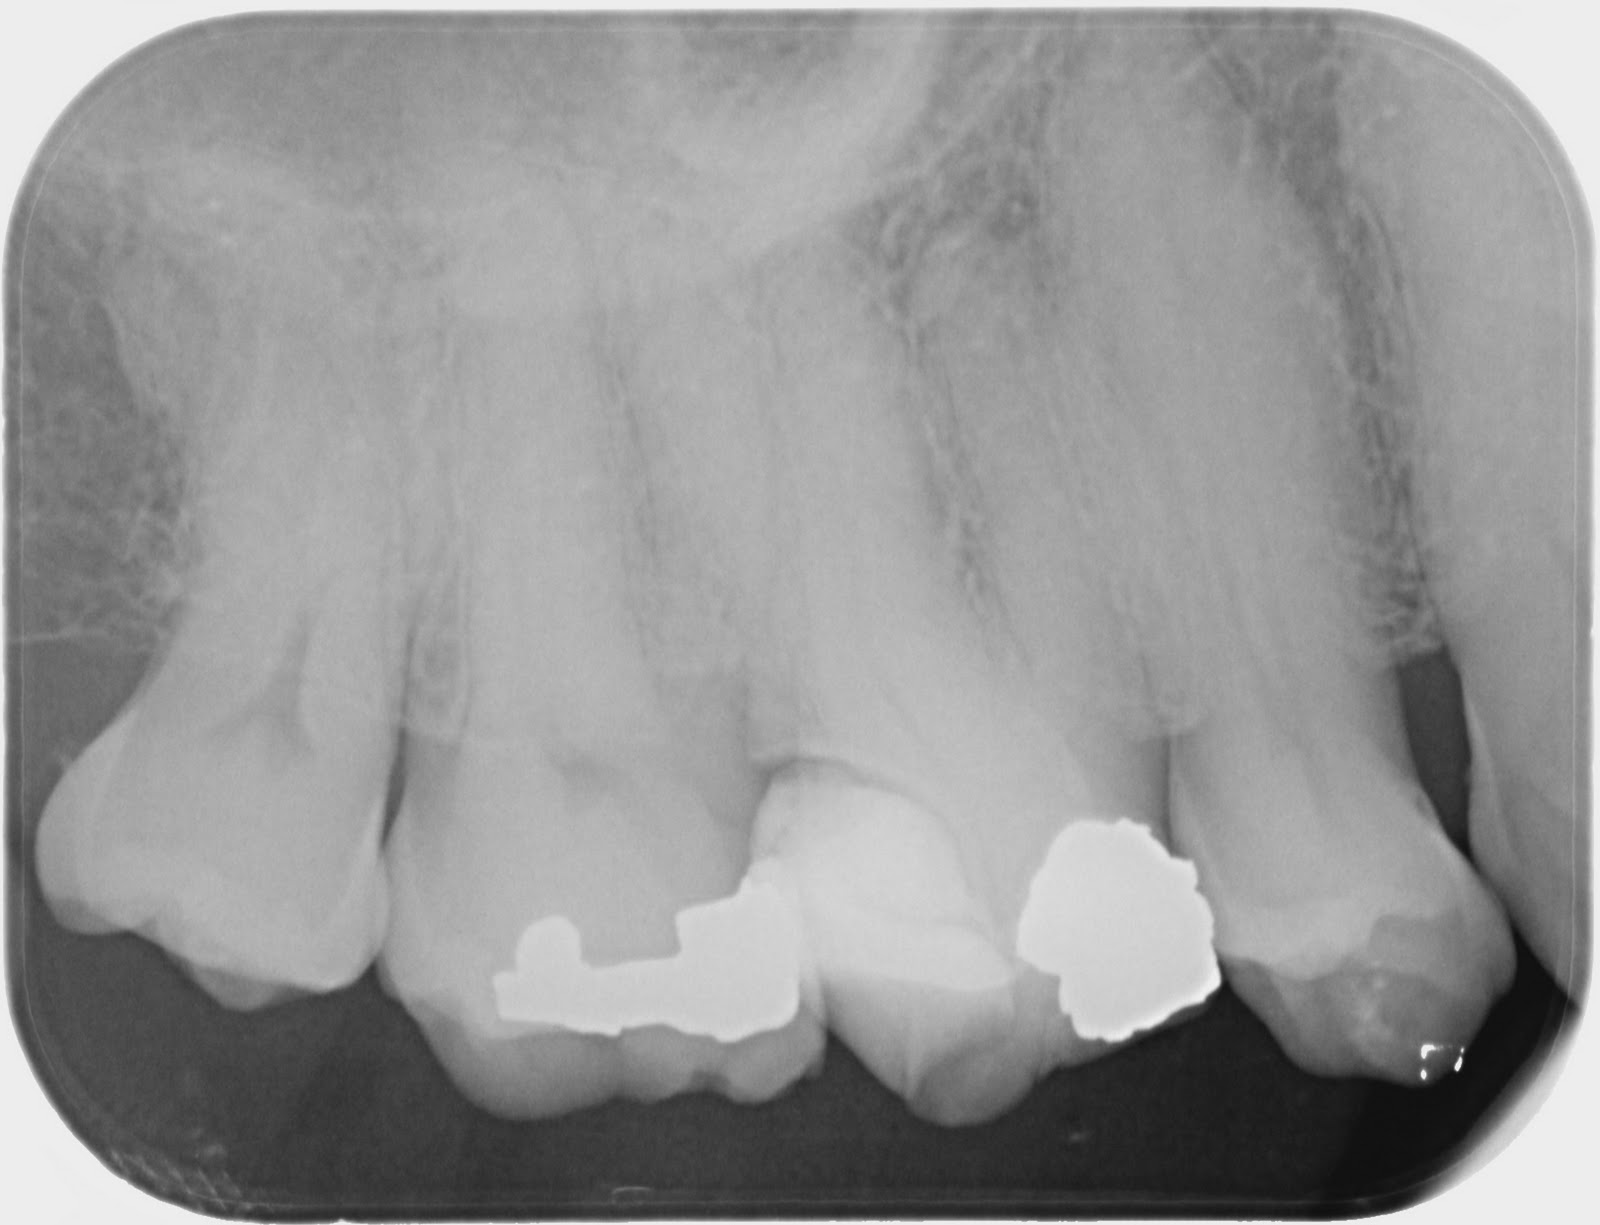

Completely Calcified Canals. SoCal Root Canal

From socal-rootcanal.com